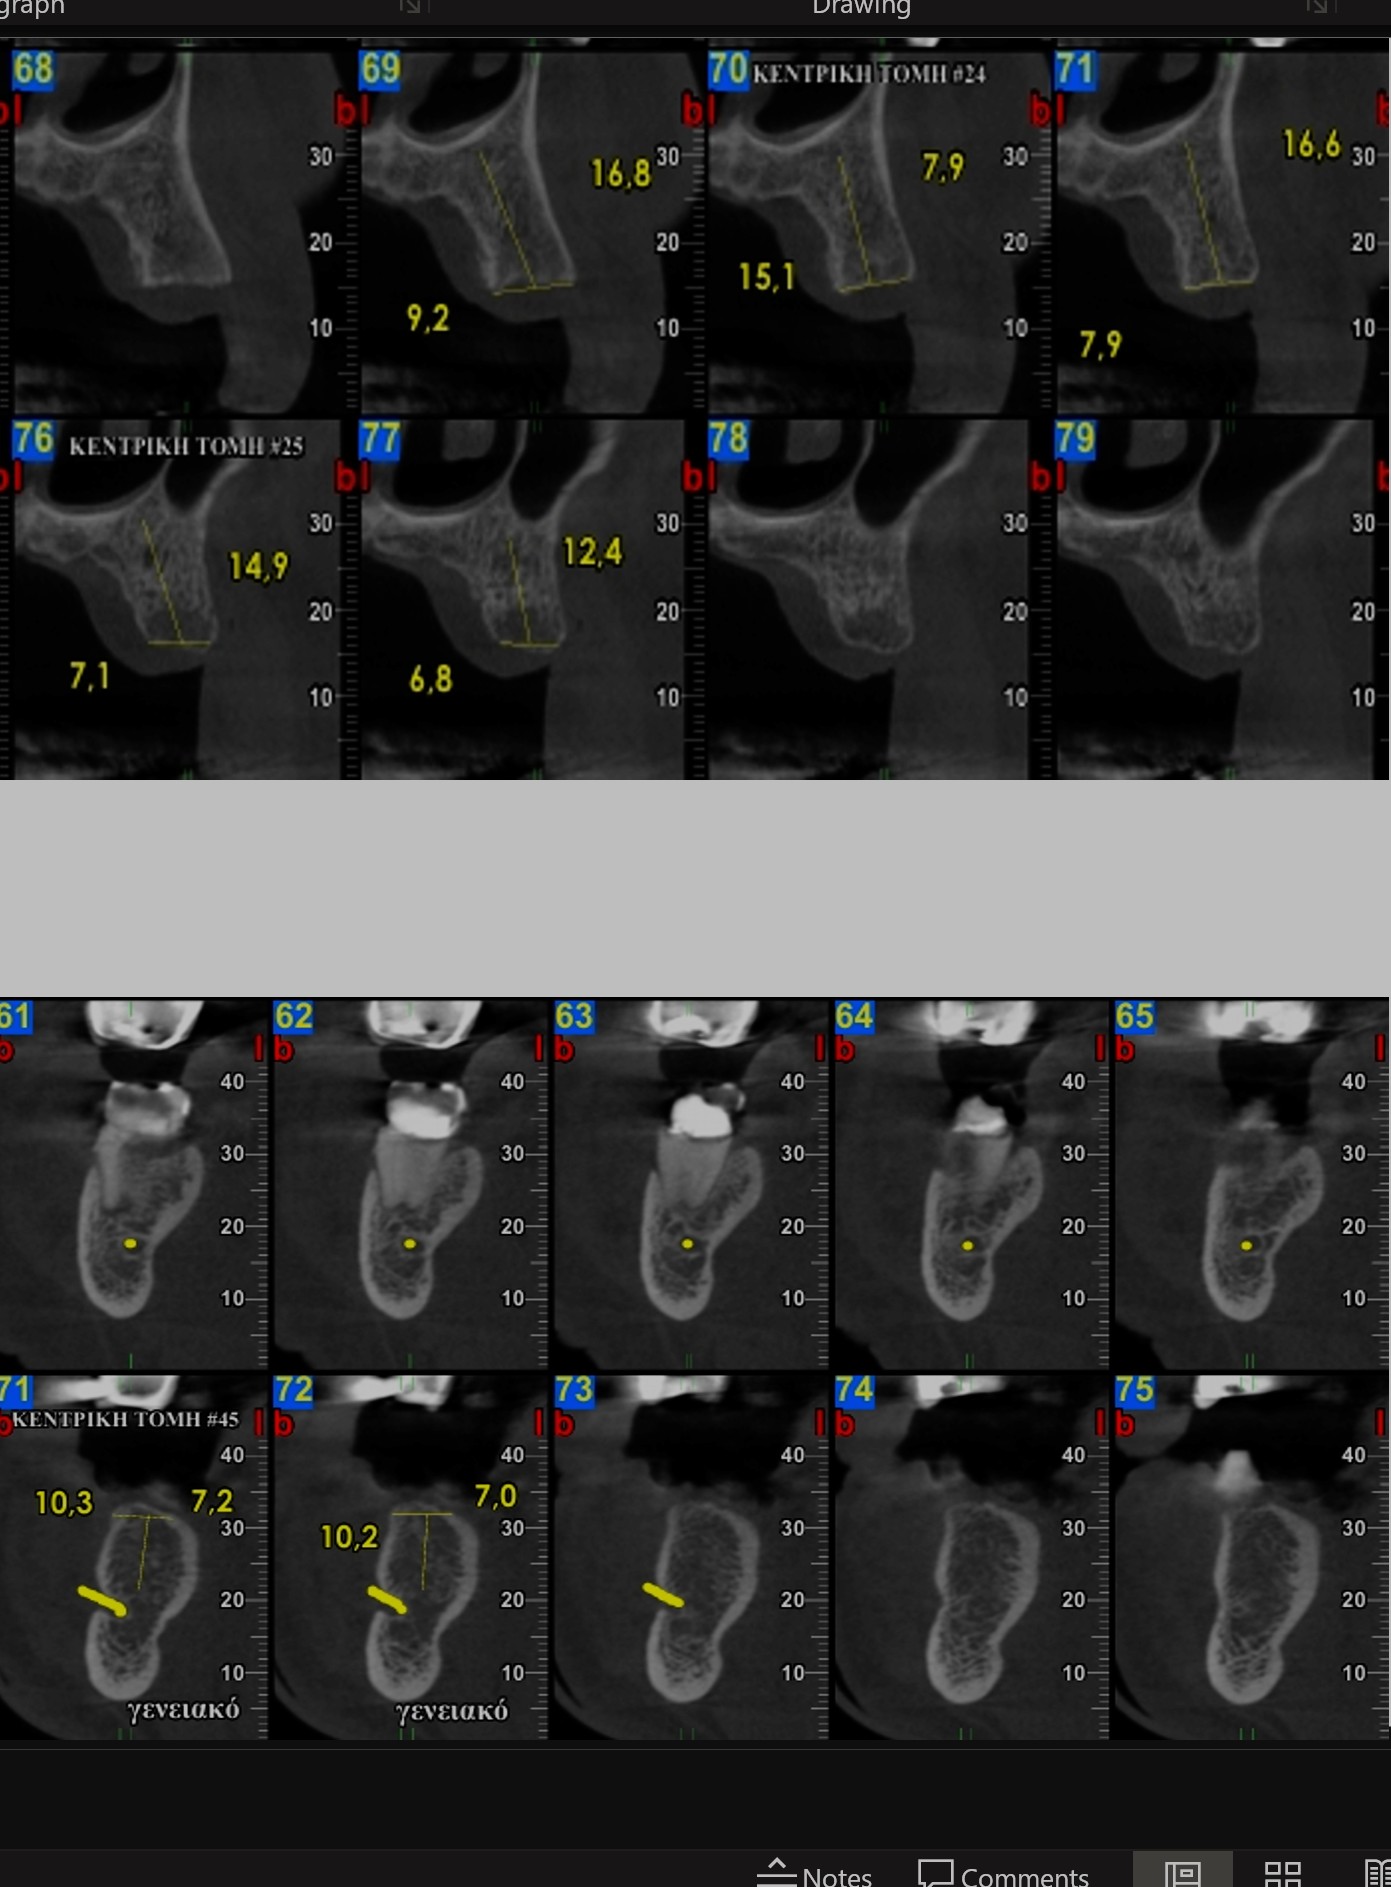

Η Ογκομετρική Υπολογιστική Τομογραφία μοιάζει με την ιατρική αξονική τομογραφία, υπερτερεί όμως αυτής, λόγω της μειωμένης δόσης της ακτινοβολίας που δέχεται ο εξεταζόμενος από τη δυνατότητα ταυτόχρονης λήψης της άνω και κάτω γνάθου, καθώς και της δυνατότητας επικέντρωσης της δέσμης ακτινοβολίας σε μικρή περιοχή της γνάθου. Παρέχει υψηλή ευκρίνεια και τη δυνατότητα πραγματοποίησης ακριβών μετρήσεων για πολλά θεραπευτικά σχέδια. Η δυνατότητα επιλογής πολλαπλών πεδίων ακτινοβόλησης από το μηχάνημά μας παρέχει αξιόπιστες εφαρμογές και για απαιτητικά οδοντιατρικά πεδία όπως ενδοδοντία, περιοδοντολογία κ.λ.π.

Η χρησιμότητα της Οδοντιατρικής Υπολογιστικής Τομογραφίας (dental scan) αναδεικνύεται μετά την επεξεργασία των εικόνων, εργασία που απαιτεί γνώση και εμπειρία. Έτσι η εξέταση εξατομικεύεται για κάθε ασθενή ανάλογα με το διαγνωστικό πρόβλημα που αντιμετωπίζεται.

Κατά την επεξεργασία των εικόνων, που προκύπτουν από την ανασύνθεση της Οδοντιατρικής Υπολογιστικής Τομογραφίας σημειώνονται στις εικόνες ανατομικά στοιχεία, γίνονται μετρήσεις και σημειώνεται και η παθολογία όταν απαιτείται.